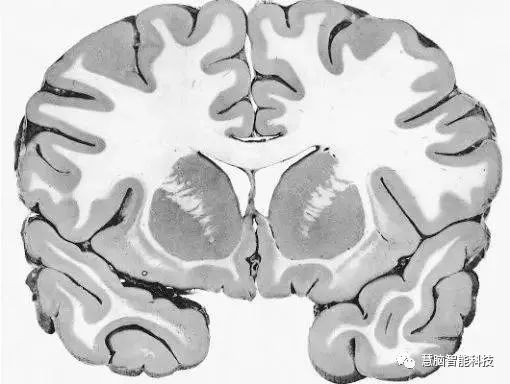

让我们使用半球横截面看看大脑的主要部分。这是你脑袋里大脑的样子:

现在,让我们把大脑取出来,并删除左半球,这让我们能看清楚内部。